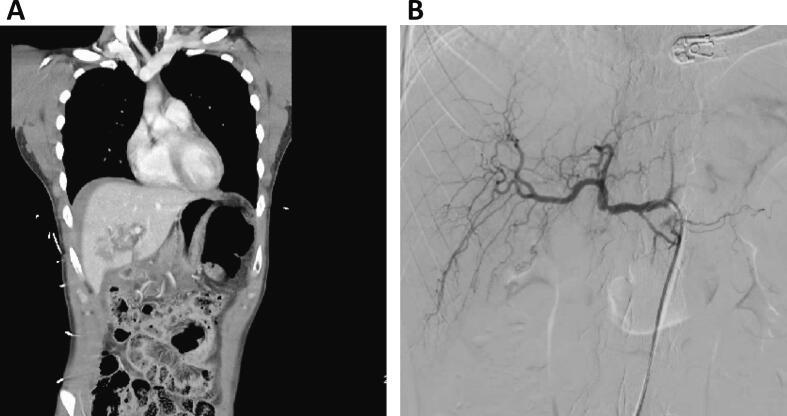

Hemorrhage is among the leading causes of death for trauma patients. Adjunct techniques used to control bleeding include use of aortic cross clamping, application of a pelvic binder, rapidly expanding hemostatic sponges, and extra-peritoneal packing. Additionally, Resuscitative Endovascular Balloon Occlusion of the Aorta (REBOA) can provide life-saving proximal control for patients with massive internal hemorrhage. This study concerns a patient treated with Zone 1 REBOA for class IV hemorrhagic shock from a spontaneous common hepatic artery rupture. REBOA was performed at bedside in the Surgical Intensive Care Unit (SICU) prior to definitive selective embolization. A healthy 28-year-old male suffered a grade 4 liver laceration and pancreatic head transection with associated duodenal injury after a high-speed motor vehicle collision. On arrival, the patient required a damage control laparotomy with multiple reoperations for management of his intra-abdominal injuries. By hospital day 11, significant visceral adhesions resulted in a frozen abdomen. On hospital day 20, the patient developed massive hematemesis, hematochezia, and class IV hemorrhagic shock. Vascular surgery was called to bedside in the SICU to perform REBOA. The patient received massive transfusion protocol while a 12 Fr sheath was inserted, and an aortic occlusion balloon was inflated in Zone 1 allowing for hemodynamic stabilization for transport and definitive management in the angiography suite. This case reports a novel use of REBOA, at bedside in the SICU, for the management of a massive gastrointestinal bleed in a patient with frozen abdomen. In this case, REBOA allowed us to achieve temporary hemodynamic stability prior to definitive control in the angiography suite. Bedside use of REBOA in the SICU prevented certain exsanguination and death.

出血是创伤患者的主要死因之一。用于控制出血的辅助技术包括使用主动脉交叉钳夹、应用骨盆固定带、快速膨胀止血海绵和腹膜外填塞。此外,复苏性血管内主动脉球囊阻断术(REBOA)可为大量内出血患者提供挽救生命的近端控制。本研究涉及一名因自发性肝总动脉破裂导致IV级失血性休克而接受1区REBOA治疗的患者。在进行确定性选择性栓塞之前,在外科重症监护病房(SICU)床边进行了REBOA。一名28岁健康男性在高速机动车碰撞后发生4级肝裂伤、胰头横断伤并伴有十二指肠损伤。入院时,患者需要进行损伤控制剖腹术并多次再次手术以处理其腹腔内损伤。到住院第11天,严重的内脏粘连导致腹部冻结。在住院第20天,患者出现大量呕血、便血和IV级失血性休克。血管外科医生被召至SICU床边进行REBOA。在插入12F鞘管时,患者接受了大量输血方案,并且在1区充盈了主动脉阻断球囊,从而实现了血流动力学稳定,以便转运至血管造影室进行确定性治疗。本病例报告了在SICU床边使用REBOA治疗腹部冻结患者大量胃肠道出血的新方法。在本病例中,REBOA使我们能够在血管造影室进行确定性控制之前实现暂时的血流动力学稳定。在SICU床边使用REBOA避免了某些失血和死亡。